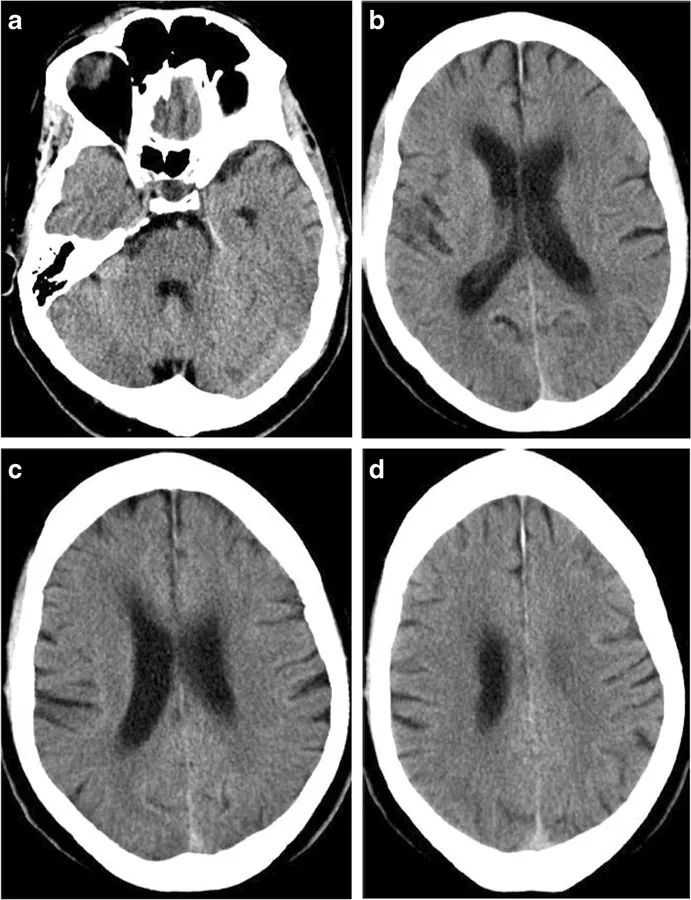

图4 乳腺癌脑转移,CT、MRI上可见广泛的血管源性脑水肿区域,侧脑室受压,中线移位。引起血管源性脑水肿的占位性病变位于左额上回。

图5 侧脑室周围可见条片状异常密度,CT上呈低密度,MRI的T2WI上呈高信号,边界较清(左、中)。本例患者的阻塞性脑积水由后颅窝占位导致(右)。